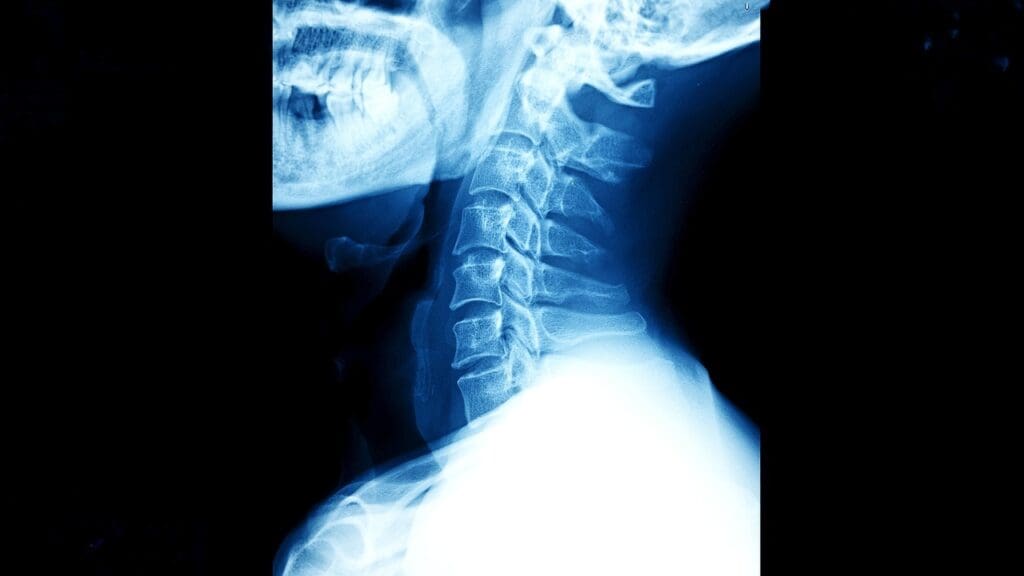

ACDF stands for Anterior Cervical Discectomy and Fusion. It’s a surgery to treat neck pain and other symptoms from cervical spine problems. ACDF spine fusion mainly helps with degenerative disc disease, herniated discs, and spine instability. It removes the bad disc and fuses the vertebrae to stabilize the spine, reduce pain, and enhance life quality.

The ACDF cervical spine surgery term is complex. “Anterior” means the surgery is done from the front. “Cervical” points to the neck area treated. “Discectomy” is the removal of the damaged disc. And “Fusion” is the joining of two vertebrae to stabilize the spine. This surgery shows the progress in spinal surgery, providing a good option for certain cervical spine conditions.